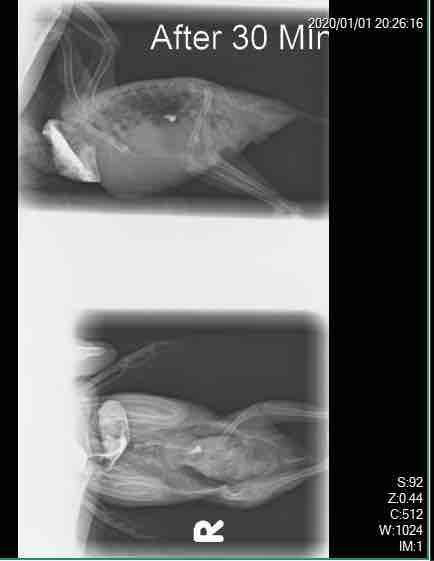

it’s been 3 days that my bird is vomiting everything he eats, from seeds to even water the verterinary after testimg his crop told me that he have both bacteria and fungi in his crop and he prescribed some medicenes that I have attached below, my bird even vomits all his drops and is getting worse and worse. I wanted to know another opinion on his illness

Thanks for reaching out about Fandogh and including images. Anti-emetic (anti-vomiting) medications can be given by injection, so might reduce/stop regurgitation, that can then allow oral medications to be given. Subcutaneous fluids might have to be given to maintain hydration. Were follow up radiographs taken after the initial ones? A gastrointestinal foreign body must still be considered. Good luck.